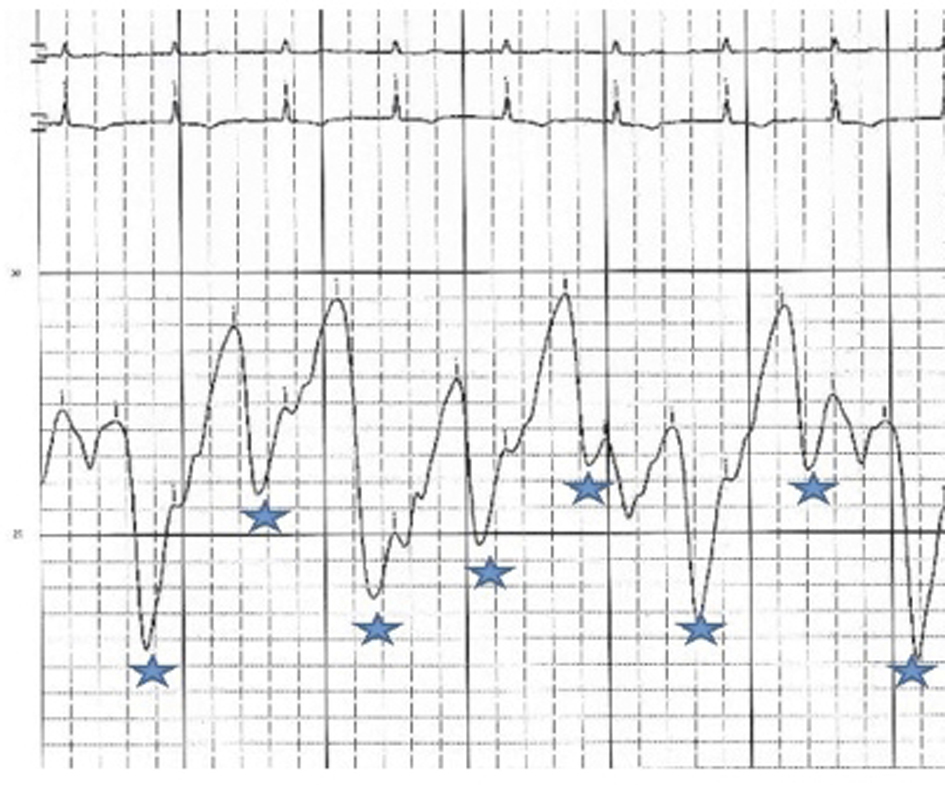

An initial complete blood count showed a mild anemia with hemoglobin of 11.2 g/dl. An anterior-posterior chest x-ray showed bilateral interstitial edema with pleural effusions. A transthoracic echocardiogram was performed and found a large pericardial effusion (Fig. 1) with tamponade physiology (Fig. 2). No intracardiac masses were noted. A right heart catheterization was also performed. The initial right atrial (RA) and intrapericardial pressures were elevated at 38 and 31 mmHg, respectively (Fig. 3). The patient underwent urgent pericardiocentesis after warfarin reversal with vitamin K and fresh frozen plasma. Approximately 1060 ml of blood-tinged fluid were removed. After pericardiocentesis there was no residual pericardial fluid assessed by transthoracic echocardiogram (Fig. 4), despite that the RA pressure remained significantly elevated at 33 mmHg. The RA tracing revealed a prominent Y descent (Fig. 5). Due to the patient’s supratherapeutic INR (international normalized ratio) and transient neurologic deterioration from sedation, simultaneous right and left heart catheterizations were not performed. The hemodynamics were compatible with effusive-constrictive pericarditis. Cytology and flow cytometry in the pericardial fluid revealed the presence of monoclonal kappa B-cells, CD 5 negative, CD 10, CD 19, CD 20, and CD 45 positive. Morphologically, the cells were consistent with large B-cell non-Hodgkin's lymphoma. A bone marrow biopsy ruled out systemic lymphomatous involvement. Positron emission tomography (PET) scan confirmed the diagnosis of primary cardiac lymphoma (PCL) showing thickening of the anterior pericardium with an standardized uptake value (SUV) of 5.0. There was no malignant uptake in any other structure such as lymph nodes, other serosal surfaces, or solid organs.

![]() Click for large image | Figure 5. RA pressure after pericardiocentesis: mean RA pressure remains high at 33 mmHg with change in the wave pattern, deep Y descents (*). |

Effusive-constrictive pericarditis is a rare form of pericardial disease that is usually diagnosed after pericardiocentesis. The hallmark is the persistence of an elevated right atrial pressure after drainage of pericardial fluid, traditionally documented by normalization of intrapericardial pressure. In our case we documented by echocardiogram with minimal residual pericardial fluid. Other classic features include reversed X/Y ratio in the atrial pressure tracing after drainage of the pericardial fluid, dip-plateau morphology in the ventricular tracings and accentuation of the interventricular interdependence. Its diagnosis is important as patients might require pericardiectomy for treatment of right sided heart failure [7-10].